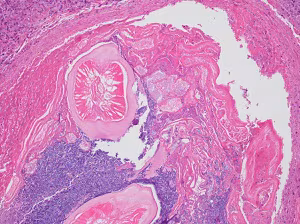

A 60-year-old non-smoking male patient presented to his primary care physician with a chronic cough and shortness of breath. He reported no recent travel outside of the Southern United States. A CT scan revealed focal consolidation and cavitation. Later, a lung biopsy was performed on a lesion that revealed possible parasitic forms on histopathological examination. Images A—C show the objects of interest in the hematoxylin and eosin (H&E) stained slides; the size of each object was approximately 200 µm in diameter. What is your diagnosis? Based on what criteria?

Figure A